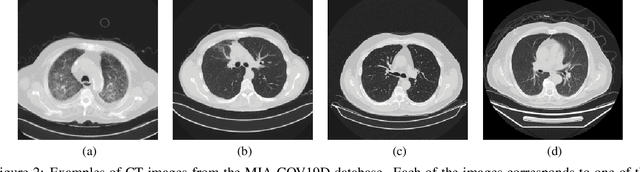

Abstract:Early and accurate diagnosis of COVID-19 is essential to control the rapid spread of the pandemic and mitigate sequelae in the population. Current diagnostic methods, such as RT-PCR, are effective but require time to provide results and can quickly overwhelm clinics, requiring individual laboratory analysis. Automatic detection methods have the potential to significantly reduce diagnostic time. To this end, learning-based methods using lung imaging have been explored. Although they require specialized hardware, automatic evaluation methods can be performed simultaneously, making diagnosis faster. Convolutional neural networks have been widely used to detect pneumonia caused by COVID-19 in lung images. This work describes an architecture based on 3D convolutional neural networks for detecting COVID-19 in computed tomography images. Despite the challenging scenario present in the dataset, the results obtained with our architecture demonstrated to be quite promising.